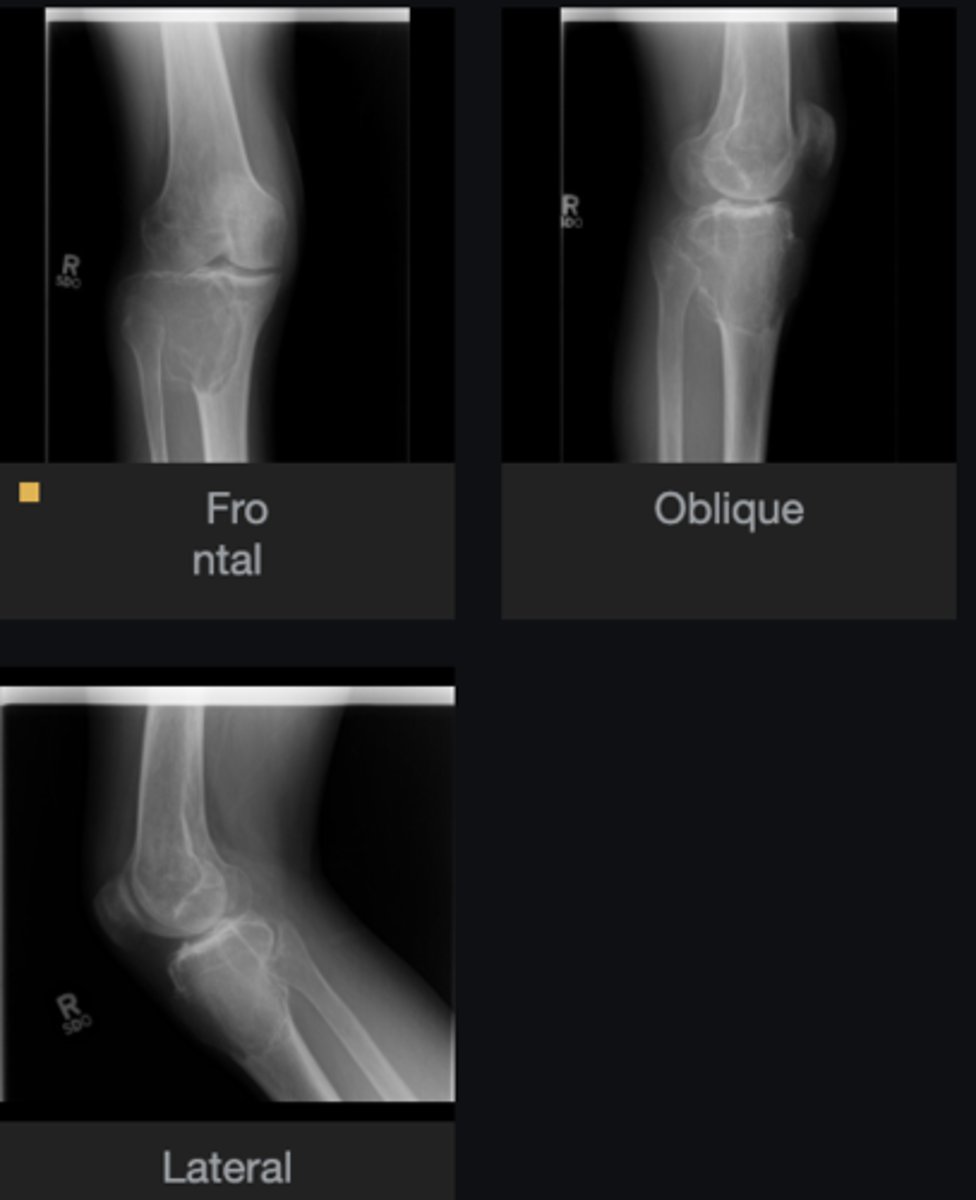

- Distal femur involved

- Elongated stalk

- Cortex and medulla are continuous

- Pointing away from joint

- Narrow base

Describe the bone lesion

<p>Describe the bone lesion</p>

Pedunculated solitary osteochondroma

Most likely diagnosis?

<p>Most likely diagnosis?</p>

Refer to orthopedist

Next step?

<p>Next step?</p>

- Fracture

- Malignant transformation (chondrosarcoma)

- Bursitis

- Neurologic injury

Concerns/complications?

<p>Concerns/complications?</p>

- Distal femur

- Metaphysis

- Anterolateral

- Broad base

- Cortex and medulla continuous

Sessile solitary osteochondroma